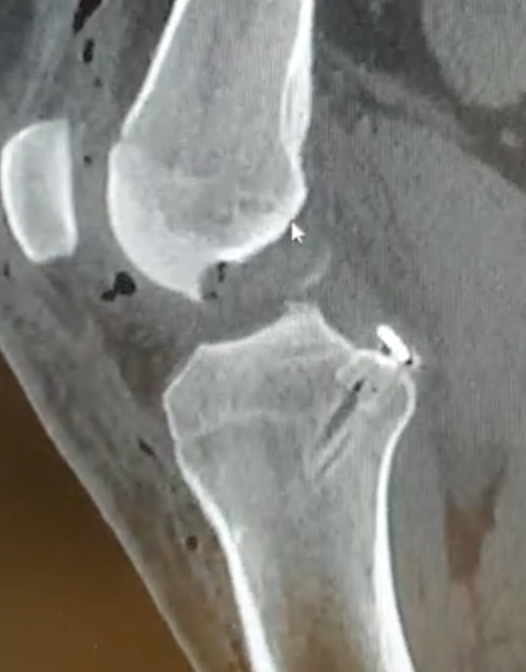

Acute femoral peel off of PCL

Acute Surgical Options

1. Repair bony avulsion

2. Acute suture repair of femoral peel off +/- augmentation

Acute repair of femoral peel off with suture tape augmentation

Indication

Femoral avulsion of the PCL

Acute injury

Technique

Repair to PCL to femoral insertion with sutures

Pass suture tape through tibial insertion to femoral insertion PCL to augment